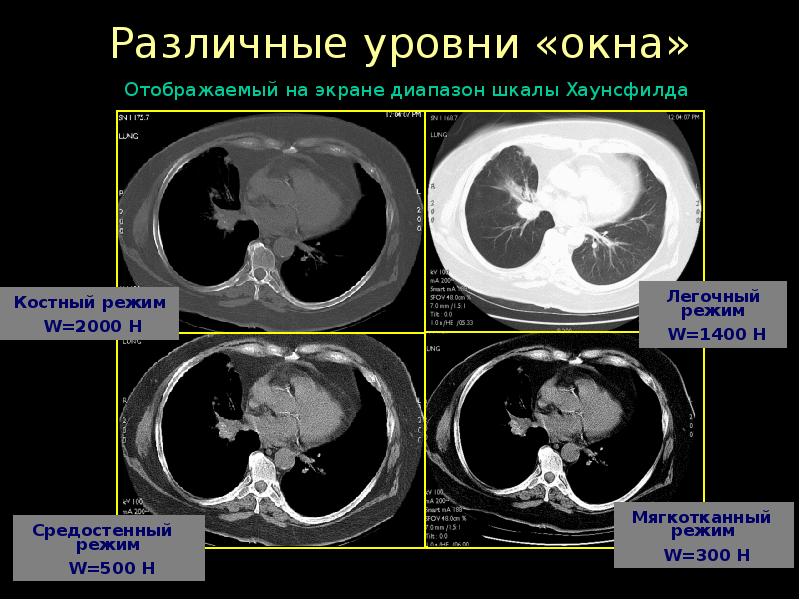

Лучевая диагностика в неврологии презентация - 88 фото